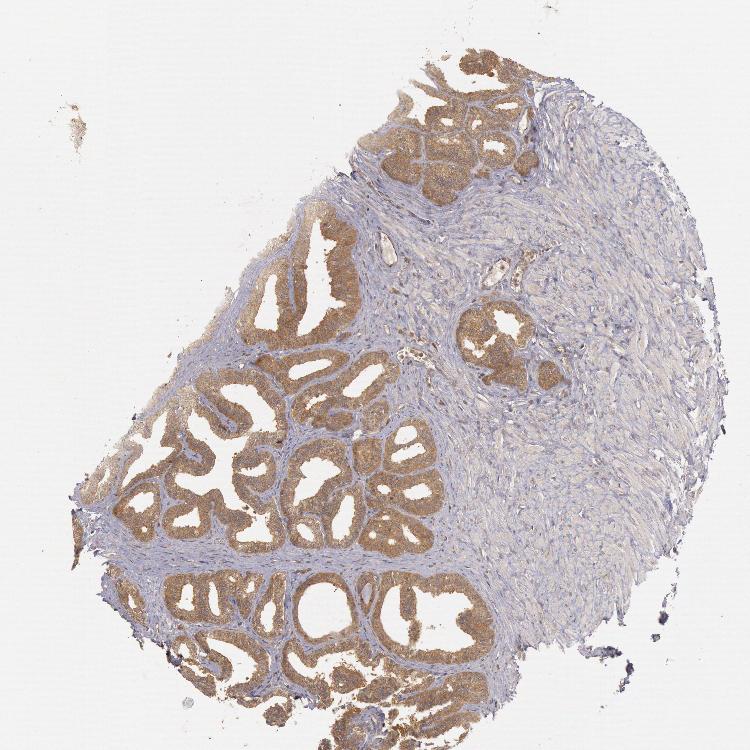

SEMINAL VESICLE - Antibody stainingi

Antibody staining in the annotated cell types in the current human tissue is reported as not detected, low, medium, or high, based on conventional immunohistochemistry profiling in selected tissues. This score is based on the combination of the staining intensity and fraction of stained cells.

Each image is clickable and will lead to virtual microscopy that enables deeper exploration of all samples and also displays staining intensity scores, fraction scores and subcellular localization as well as patient and tissue information for each sample.

Antibody HPA001328Antibody HPA071048Antibody CAB004552Antibody CAB080447Antibody CAB080451Antibody CAB080531

Glandular cells HighMediumMediumLowLowHigh